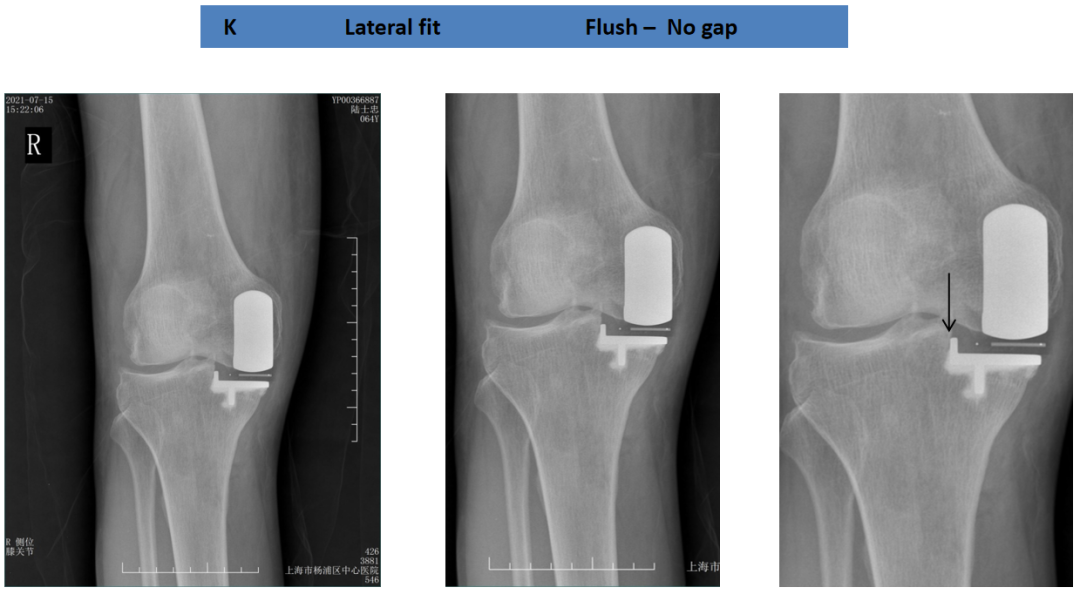

胫骨平台内外覆盖(冠状位)

胫骨假体对胫骨截骨面的覆盖:内侧缘齐平,假体完全覆盖胫骨平台。

胫骨假体完全覆盖胫骨截骨面:假体完全覆盖胫骨平台,与侧壁无间隙。